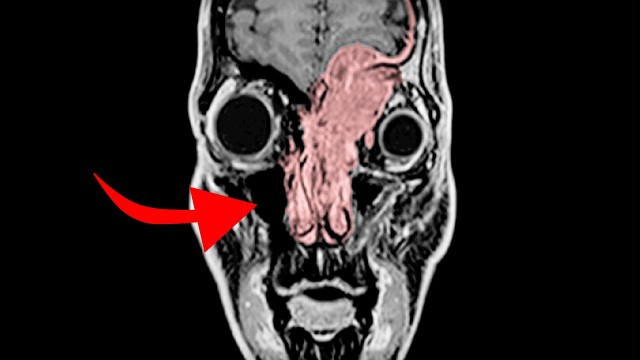

• S2020E16 A Mom Ate 5 Day Old Sushi For Dinner. This Is What Happened To Her Brain.

The greatest sushi of all time Patient JC portrayed by Anna Fagan